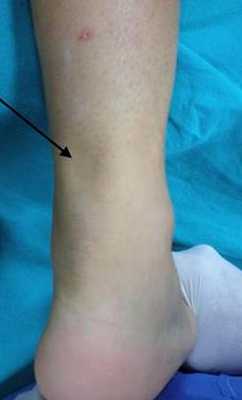

Пациентка Х.65 лет. Получила разрыв ахиллова сухожилия после длительного течения тендинита ахиллова сухожилия. Хирургическое лечение не было предложено пациенте ввиду её преклонного возраста и сопутствующей патологии. На этой фотографии дефект ахиллова сухожилия виден невооружённым взглядом.

При осмотре обратили на себя внимание выраженная атрофия икроножной мышцы, пастозность в зоне расположения ахиллова сухожилия. Тест пассивной плантарфлексии выявил значительные различия в положении стопы при расслабленном положении.